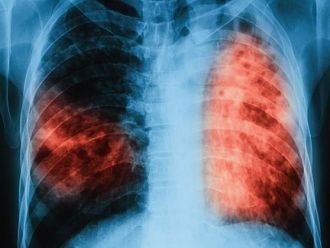

Превенцията, лечението и грижите за болните от туберкулоза не трябва да отслабват по време на епидемията от COVID-19, защото всяко пренебрегване може да има лоши поледици както за пациентите, така и за общественото здраве. Това е основната препоръка, която експертите на Световната здравна организация (СЗО) отправят към политиците и медицинската общност в обширен информационен материал, третиращ отделните аспекти на работата с пациенти, засегнати или застрашени от туберкулоза в условията на широко разпространение на SARS-CoV-2 в цял свят и нарастващ брой болни от COVID-19.